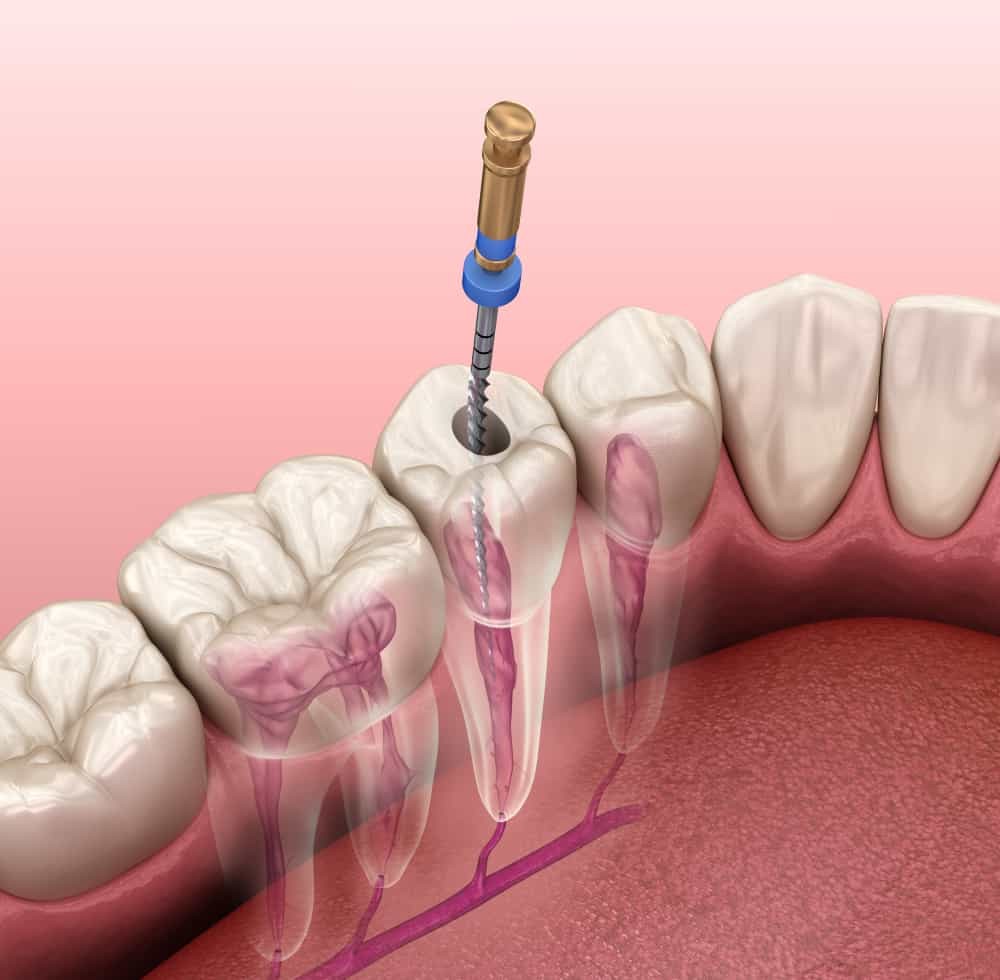

عصب کشی

وقتی پالپ دندان های شما در حال از بین رفتن باشند و دندان ها در حال پوسیده شدن باشند و عفونی شوند، شما به عصب کشی نیاز خواهید داشت. دندانی كه به اين روش درمان، نياز پیدا می کند ممكن است به رنگ قهوه اي درآید و در همان رنگ بماند. این اتفاق به دلیل این است که ریشه از بین رفته، تیره شده و به دندان سرایت می کند.